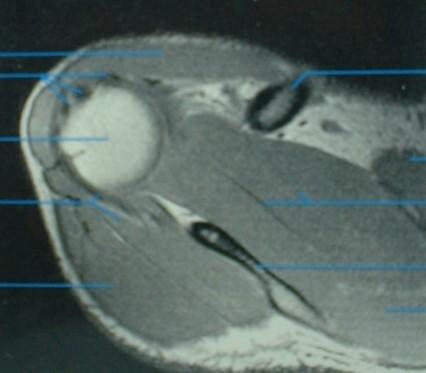

RESONANCIA MAGNETICA

Resonancia magnética

Corte sagital

Resonancia magnética Corte axial

Corte coronal